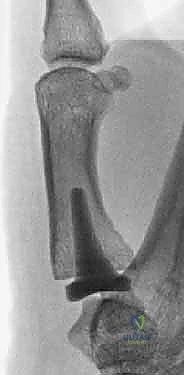

2. التصوير الإشعاعي وتصنيف إيتون-ليتلر (Eaton-Littler Classification)

تُعد الأشعة السينية (X-rays) أداة ضرورية لتأكيد التشخيص وتقييم مدى الضرر. يستخدم الدكتور هطيف تصنيف "إيتون-ليتلر" العالمي لتحديد مرحلة المرض، والذي يبني عليه قرار التدخل الجراحي:

* المرحلة الأولى (Stage I): اتساع طفيف في مساحة المفصل (دليل على التهاب الغشاء الزلالي وتراخي الأربطة)، الغضروف لا يزال سليماً، ولا توجد نتوءات عظمية.

* المرحلة الثانية (Stage II): تضيق بسيط في مساحة المفصل (بداية تآكل الغضروف)، مع ظهور نتوءات عظمية صغيرة (أقل من 2 ملم)، وبداية انزلاق المفصل.

* المرحلة الثالثة (Stage III): تضيق شديد أو انعدام لمساحة المفصل (احتكاك عظم بعظم)، نتوءات عظمية كبيرة (أكبر من 2 ملم)، انزلاق واضح للمفصل، وتصلب العظام تحت الغضروف.

* المرحلة الرابعة (Stage IV): دمار كامل للمفصل القاعدي (CMC joint) ويمتد التلف ليشمل المفصل المجاور بين العظم المربعي والعظم القاربي (Scaphotrapezial joint).